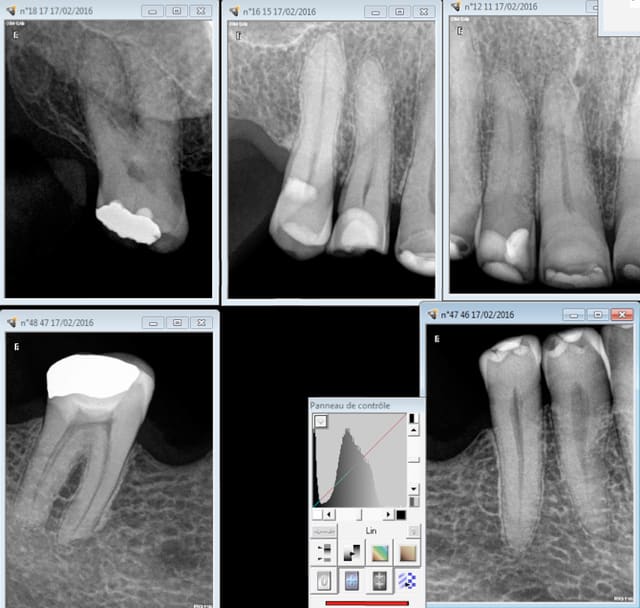

Bon là il y a les quatre 6 en moins, et quasiment toutes les autres dents on un soin plus ou moins profond + une tendance à l'abrasion. Bien que cette notion de soins intensifs ne soit pas définie je trouve que c'est pas mal. -)

Capture d e cran 2016 02 17 20.28 - Eugenol

Capture d e cran 2016 02 17 20.29 - Eugenol

Capture d e cran 2016 02 17 20.34 - Eugenol

Capture d e cran 2016 02 17 20.39 - Eugenol